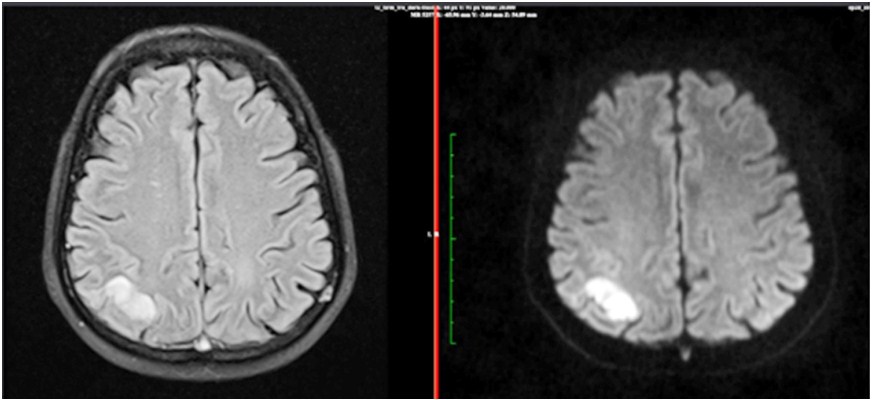

Background: Othello syndrome (OS) also known as morbid jealousy has been associated with substance use disorders, various psychiatric and neurological conditions. Case Summary: Here, we present a case of a 47 year old male who developed delusion of infidelity as sequelae of a right parietal lobe venous infarc. Discussion: Our patient had developed OS subsequently after right parietal lobe infarct. However, not many case reports have been previously documented wherein a patient developed delusion of infidelity with parietal lobe lesions. Conclusion: Hence, our case may be indicative of role of parietal lobe in the pathophysiology of delusion of infidelity, which warrants further research.

Othello Syndrome; Delusion of Infidelity; Right Parietal Lobe.